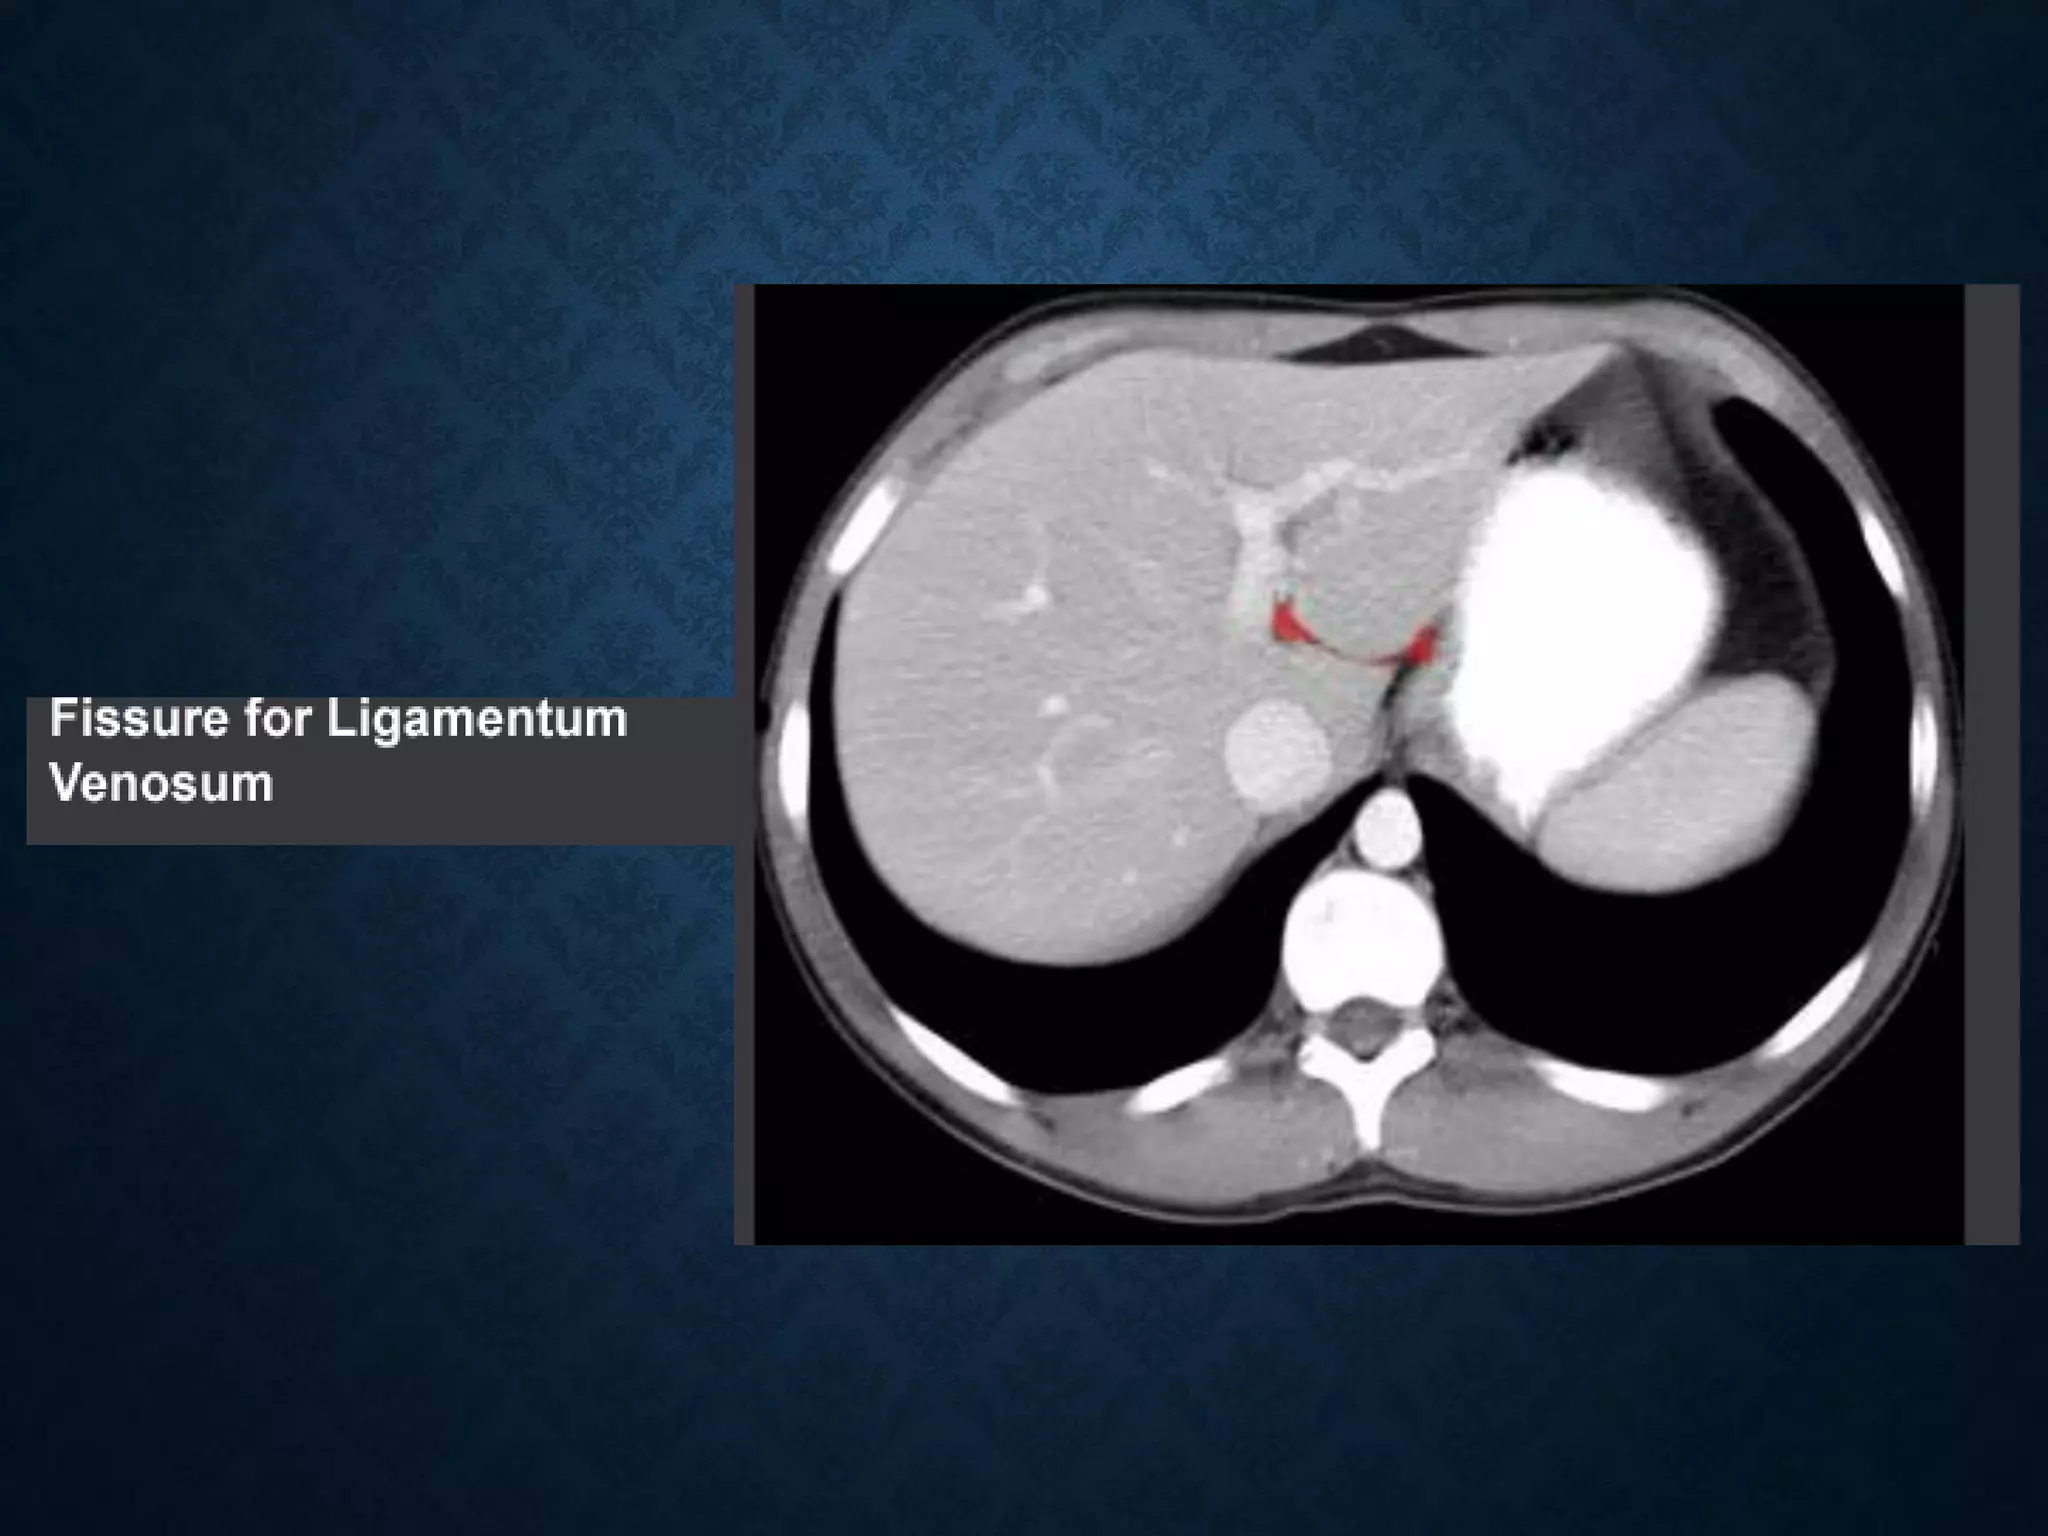

Identify the following structures in the body CT to the right. To view the location of the structure in the image click on

the label at the left and the structure will be indicated in the image. Abdominal CT scans typically begin just above

the diaphragm, so the first slice you see is of the lower chest.